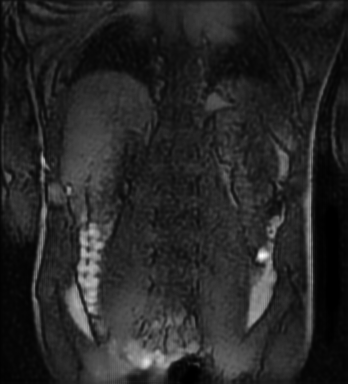

Tables 1 and 2 show our quantitative results: PSNR between the style (image we want to transfer style from) and generated image, SSIM and MS-SSIM between the content (image we want to take structure from) and generated image and finally, our proposed weighted SSIMs. For each style transfer direction and metric, our method consistently outperforms the other approaches. Figures 2 and 3 qualitatively highlight the good results of our method on 2D and 3D datasets. In addition, quantitative results on both figures show that our proposed metric preserves qualitative ordering of results for both style and content. In comparison, metrics such as SSIM struggle to accurately correlate to visual results.

Qualitative evaluation shows that the proposed method leads to sharper images, better content preservation, better localised CE and realistic MRI appearance. Quantitatively, we outperform the other algorithms with each metric, for each style transfer direction. While we expected that adding CE to images would be an easier task than removing CE, we found that for both tasks the method exhibits similarly performing quantitative and qualitative results. The results for style transfer with the kidney data show that when there is clear CE, it is easier to perform style transfer in both directions. However, when style transfer is performed on the prostate data, the model struggles in comparison to the kidney data. This may be due to the enhancement of the prostate being less defined than the kidney data. In figure 3(b), we can see the prostate with CE. Compared to figure 2(b) showing kidneys with CE, it is harder to determine the edges. The two original images shown in figures 3(a) and 3(b) are clear and easy to see some edges of prostate, in other images, it is harder to see the edges of the prostate.